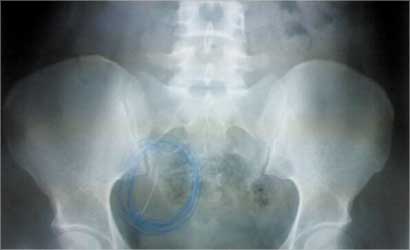

اشعة تبرز وجود الابرة في رحم (ن)

الله يساعدج ويشفيج إن شاء الله وتتخلصين من الآلام. كلمة حق لازم أقولها. ترى الرحم مافي داخله اعصاب عشان تحس بألم لما يكون داخله إبرة. الوحدة لما تولد تحس بآلام من تقلصات عضلات الرحم. ثانياً واضح من الأشعة ان الجسم الغريب (او الإبرة) برة الرحم وفي الغالب انها في الامعاء مثل ما قالت الممرضة، ثالثاً عملية التنظيفات ما يستخدم فيها ابر.

في وقت برأ فيه الدكتور بدر العنزي الاخصائي في الجهاز الهضمي والمناظير ساحة المرأة من التهمة التي سبق لزملائه الاطباء في مستشفى الجهراء بتوجيهها إلى السيدة على انها ابتلعت الابرة، وقال: «لا... الابرة لم تدخل المكان الذي استقرت فيه في رحمها عن طريق الجهاز الهضمي نهائياً».

السيدة (ن) التي أجريت لها عملية اجهاض في نوفمبر من العام 2005 في مستشفى الجهراء نفسه نسي الاطباء حسب ما أفادت به لـ «الراي» ابرة في رحمها والتي ترقد حاليا في الجناح رقم (11) في مستشفى الجهراء قالت لـ «الراي» ان «لهجة الأطباء تغيرت بعد ان سلطت «الراي» قضيتها في عدد أمس حيث عادها في الصباح الباكر مدير المستشفى بالإنابة حيث قال لشقيقها «ليش مكبرين الموضوع؟» فيما أبدى طبيب آخر استعداده لاجراء عملية لإزالة الابرة... وهذا ما يتناقض مع اللغة التي كنت اسمعها دائما عند مراجعتي للمستشفى وابلاغهم عن الآلام في بطني حيث كانوا يقولون آلام عادية وستزول قريباً».

واستغربت المريضة (ن) من كلام الطبيب الذي أعرب عن استعداده لاجراء عملية بقوله: «ما ندري الابرة هي تحت اللحم أو بالجلد أم بالعضلة».

وتساءلت: «هي العملية تنجيم أم تحديد مكان الابرة واجراء عملية؟».